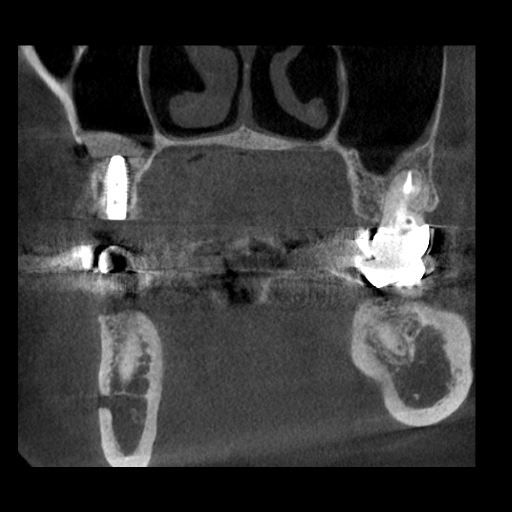

右上インプラント治療に伴うサイナスリフトの症例

Before

After

治療内容

右上の5番を抜歯され、インプラント治療を希望された患者様です。

副鼻腔があり、インプラントを埋入するための骨の量が足りないため、副鼻腔に骨を作る処置(サイナスリフト)を行い、同時にインプラント埋入しました。

理想的な位置にインプラントを埋入することができ、長期予後を獲得することができます。

担当歯科医師:平沼 佳朗

治療期間・回数

約10か月

費用

サイナスリフト込み¥671,000

リスク・副作用

術後に痛みや腫れ、出血を伴います。

口腔内の清掃不良によりインプラントの歯周病(インプラント周囲炎)になる可能性があります。定期的なメインテナンスが必要です。